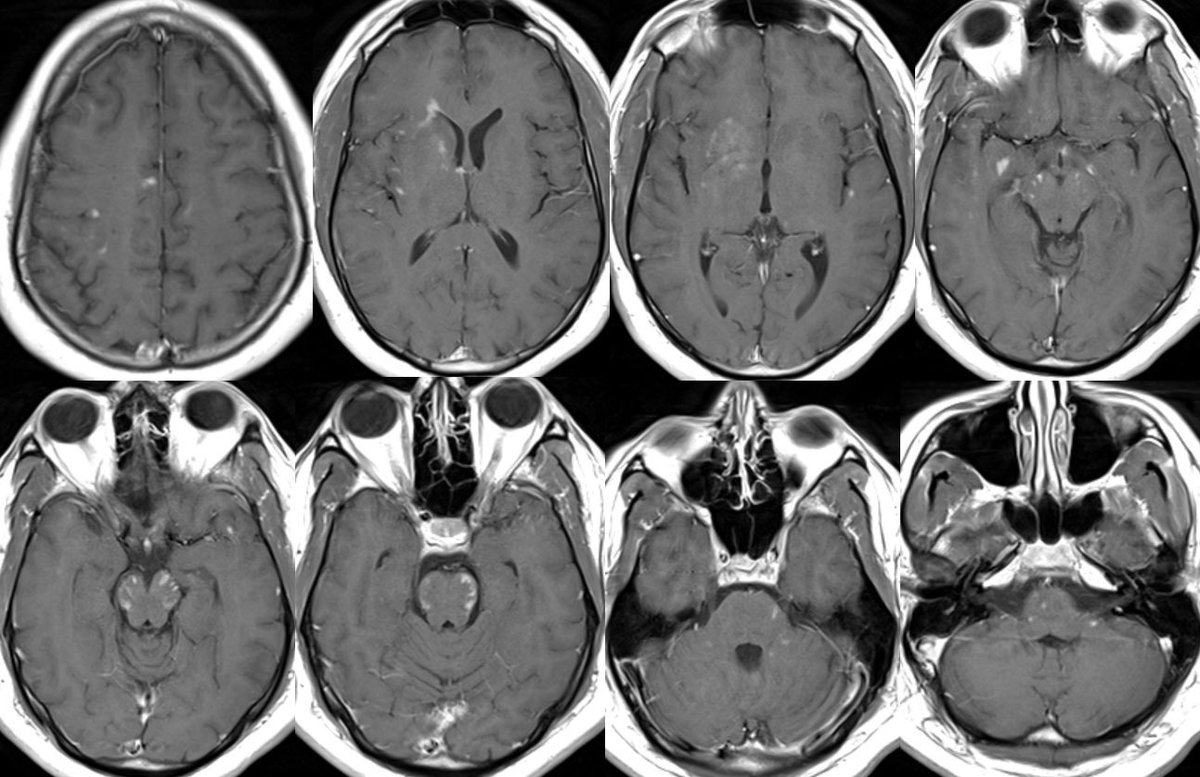

Answer: FUEL “FLAIR-variable unilateral enhancement of the leptomeninges” in MOGAD

🔷Typical Imaging of MOG-AAD:

▶️OPTIC NERVES: Long segment BILATERAL edematous & tortuous optic nerves predominantly involving the ANTERIOR nerves x.com

▶️BRAIN findings: Occur in <50% of patients though tend to involve the deep gray matter and infratentorium (particularly in children)

▶️Patterns include ADEM-like or CLIPPERS-like imaging features

▶️Leptomeningeal enhancement can also be seen in association with FUEL & FLAMES x.com

🔷A distinct subtype/clinicoradiographic syndrome of MOGAD is a cortical encephalitis presenting with headache, fever and seizures known as FLAMES of MOGAD🔥

🔷When the predominant imaging features are leptomeningeal enhancement with little to no cortical involvement, this is considered FUEL of MOGAD ⛽️ x.com

🔷FUEL ⛽️& FLAMES 🔥

▶️Imaging: Unilateral (more common) or b/l cortical swelling (🔥) or isolated leptomeningeal enhancement (⛽️) +/- other features of MOGAD